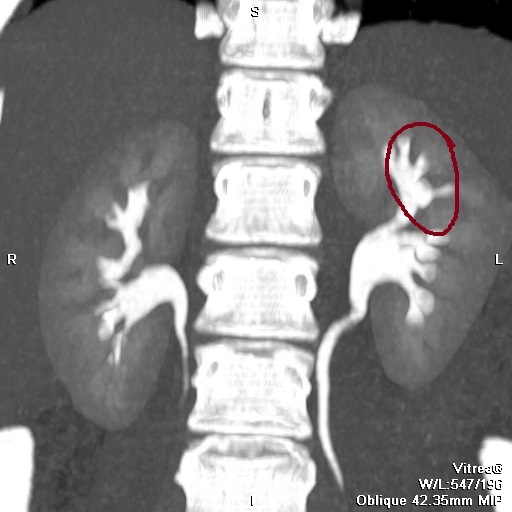

На КТ это выглядит следующим образом:

КТ ОБП в экскреторную фазу исследования: отчетливо визуализируется "отшнуровавшаяся" верхняя чашечка, иногда это называется дивертикулом чашки.

Главным отличием дивертикула чашечки от солитарной кисты является его сообщение с полостной системой почки.

В данном случае представлен дивертикул нижней чашки (указан стрелкой). МСКТ ОБП в экскреторную фазу исследования. Причина дивертикула здесь в дисфункции мышечного сфинктера шейки чашки.Контрастное вещество выполняет дивертикул и ЧЛС левой почки